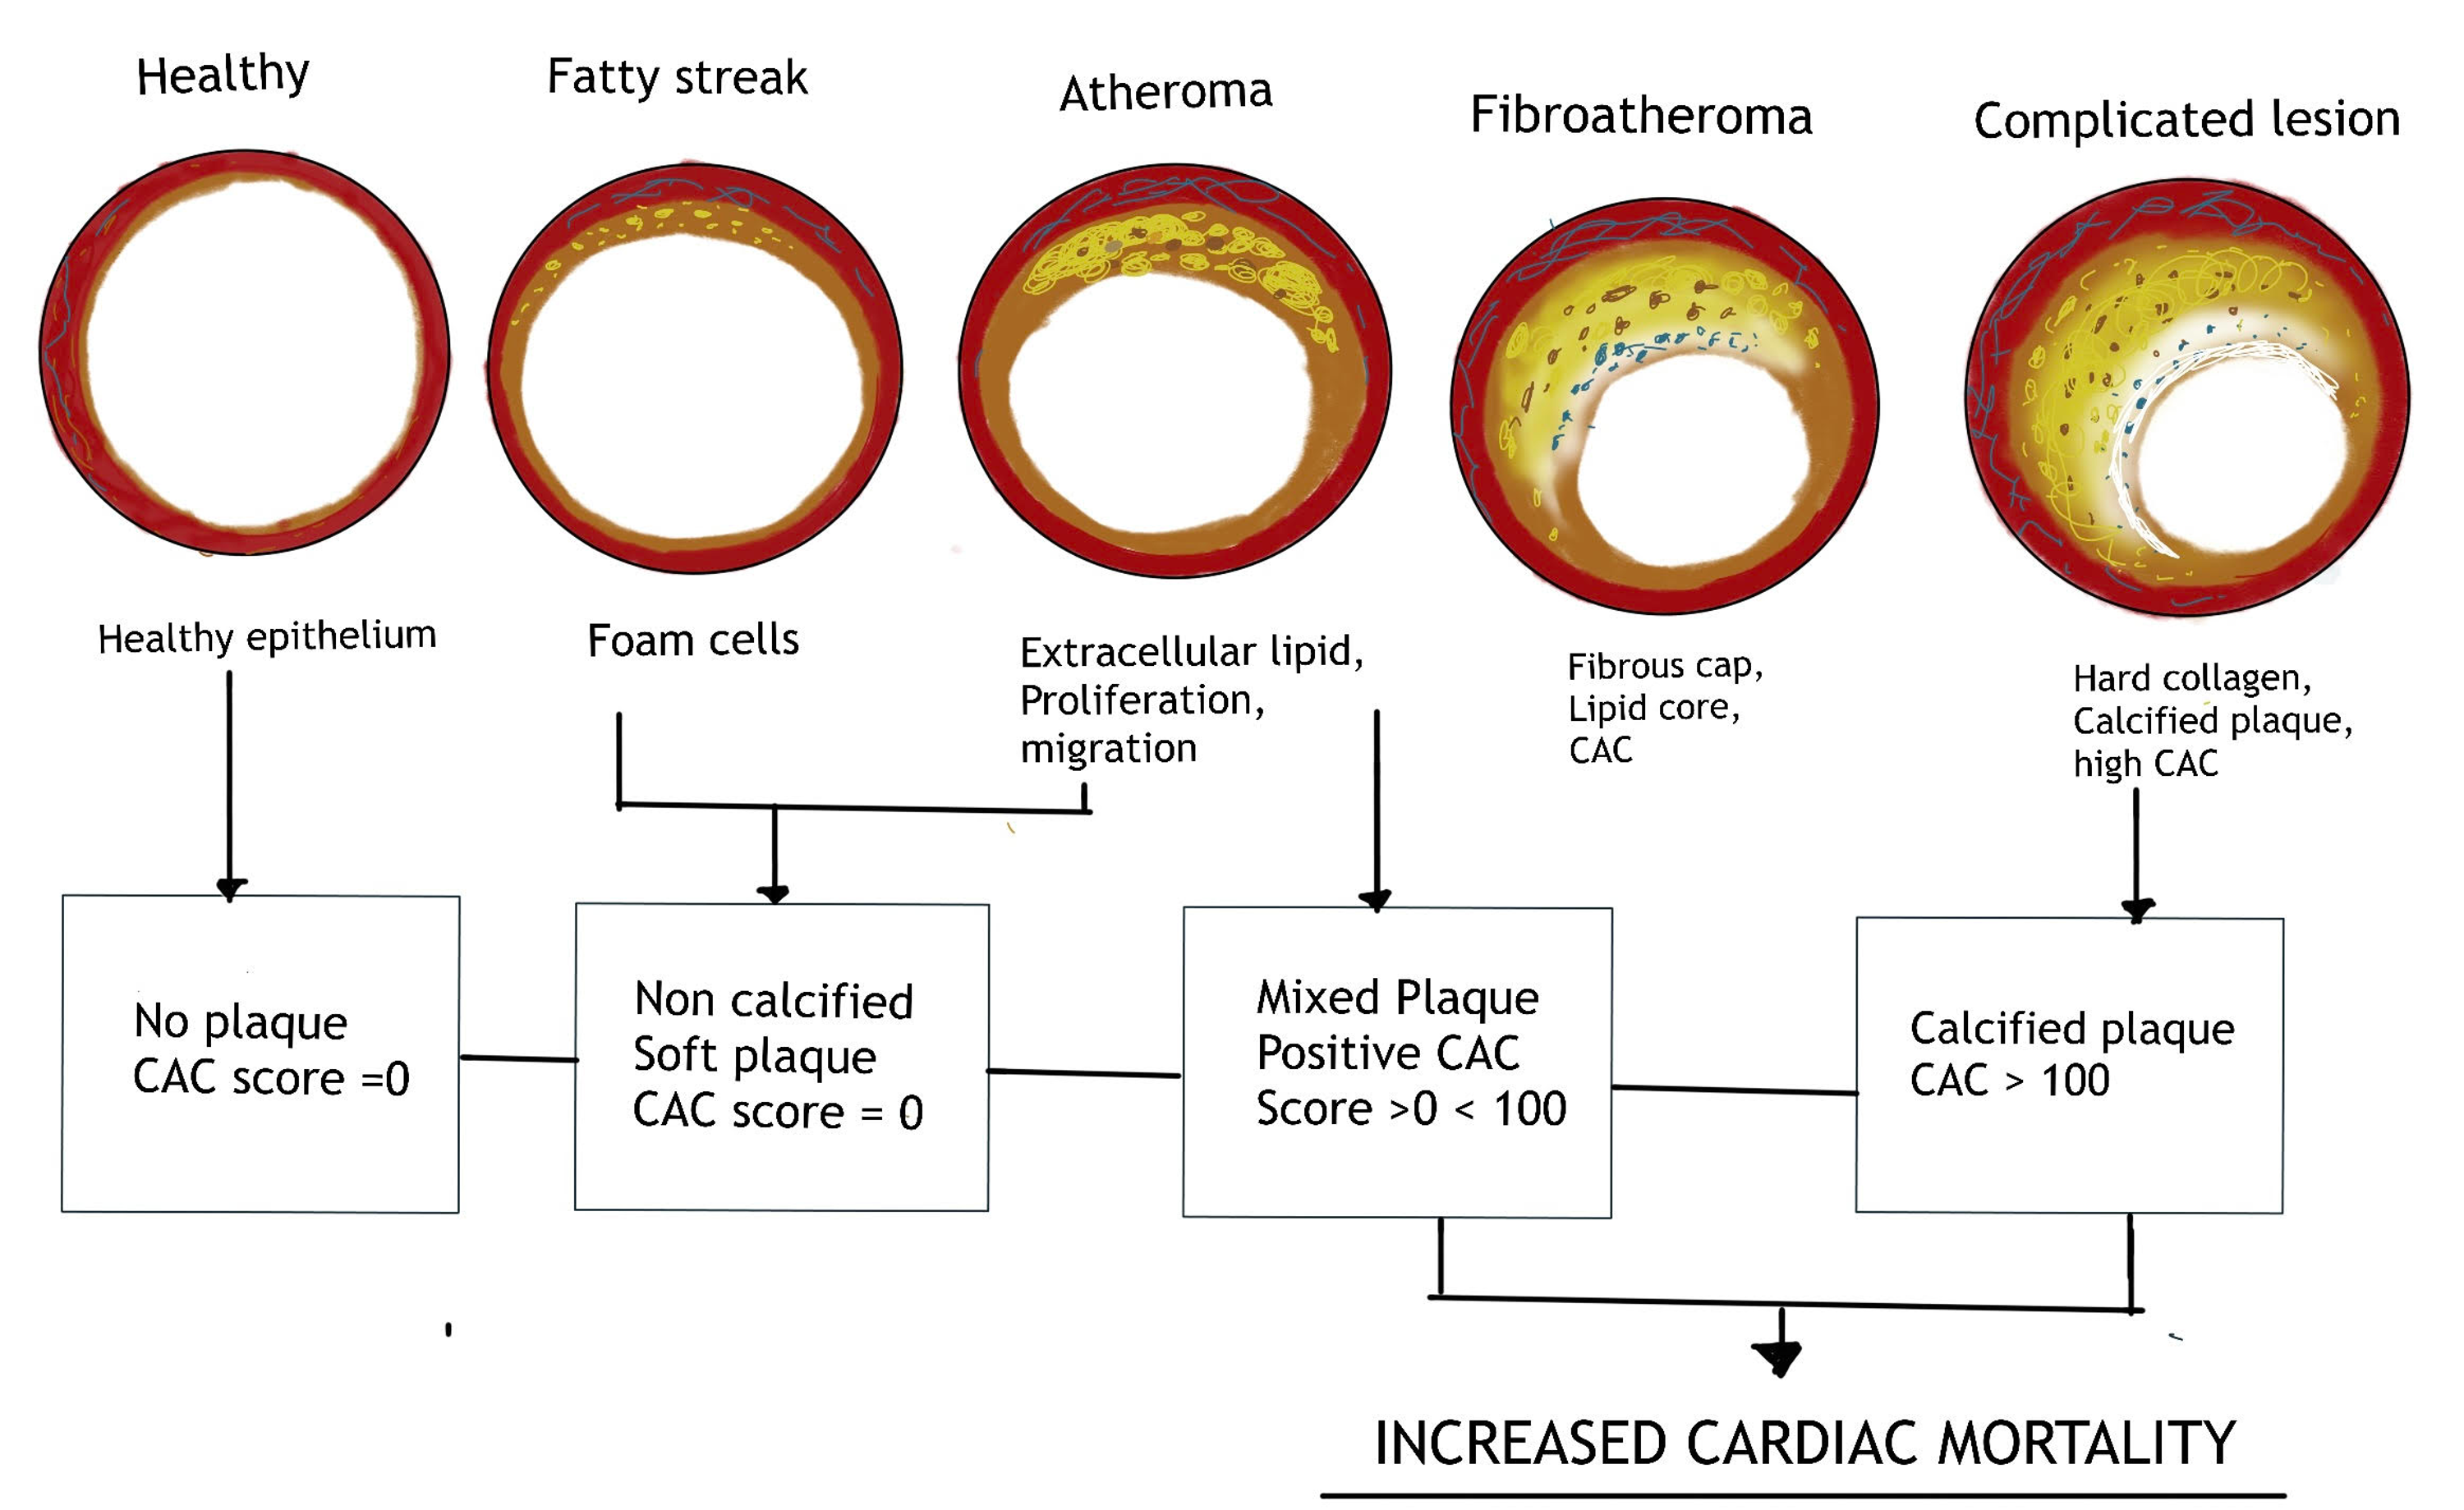

Cureus | Coronary Artery Calcium Score - A Reliable Indicator Of

www.cureus.com

www.cureus.com

Cureus | Coronary Artery Calcium Score - A Reliable Indicator Of

www.cureus.com

www.cureus.com

(PDF) Coronary Artery Calcium Score - A Reliable Indicator Of Coronary

www.researchgate.net

www.researchgate.net